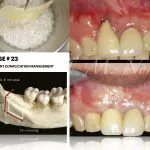

Pinhole Surgical Technique, breakthrough gum grafting alternative treatment for gum recessions…